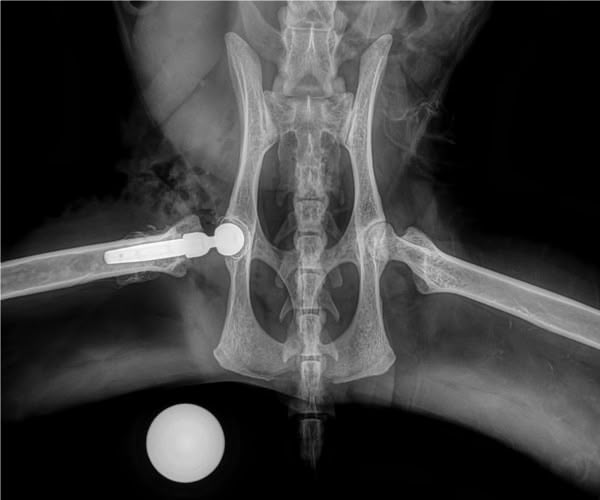

Figure 1

Figure 2